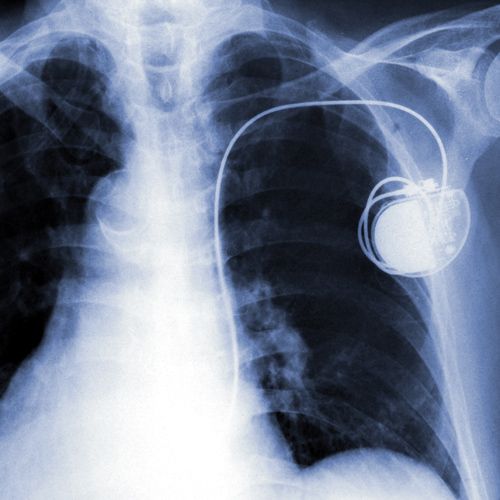

Data on man’s pacemaker led to his arrest on arson charges (ABA Journal0 http://buff.ly/2kDdaTv pic.twitter.com/zKH0jCer4D